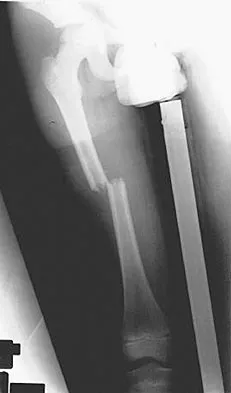

Figure 36 shows the radiograph of a patient who has hip pain and is unable to ambulate. What is the most appropriate management for this patient?

Explanation

The patient has a periprosthetic fracture of the greater trochanter - Vancouver A. The reason for the fracture of the greater trochanter is the extensive periarticular osteolysis that has occurred as a result of polyethylene wear. The latter is demonstrated by eccentric seating of the large femoral head in the acetabulum. The most appropriate management is to reverse the osteolysis process, which involves exchange of the acetabular liner with or without revision of the other components depending on their fixation and position. The greater trochanter can also be fixed during revision surgery. Duncan CP, Masri BA: Fractures of the femur after hip replacement. Instr Course Lect 1995;44:293-304.